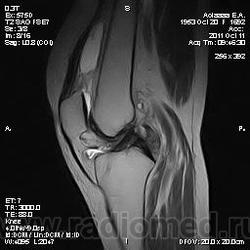

Дискуссия о природе "структры" в проекции передней поврехности метадиафиза бедренной кости.

Две версии: А. костно-хрящевой экзостоз. Б. разрастания сумки.

Пациента на МРТ прислали с травмой. "Это" было выявлено в ряду другой патологии как случайная находка. Рентген не было возможности сделать - дистанционная диагностика. Хотя это конечно была первая мысль. Спасибо за внимание к посту.

Окончательное мнение - костно-хрящевой экзостоз. Прилагаю РКТ коленного сустава (пациент не тот, что на МРТ)

Валентин Львович, хочу обратить Ваше внимание, что это два разных кейса со сходной на мой взгляд патологией - костными экзостозами (другую временно опускаем) - взгляд со стороны МРТ и РКТ

Давайте разберемся, уважаемые коллеги, что в данном случае понимаем под термином "экзостоз": 1. опухоль - остеохондрому (костно-хрящевой экзостоз), остеому; 2. дегенеративно-дистрофические изменения (остеофиты, оссификаты в точке прикрепления сухожилий и т.д.). Внутрисуставной хондроматоз к "экзостозам" отношения не имеет

Если в демонстрации предполагается костно-хрящевой экзостоз, т.е. остеохондрома, то:

"Строение остеохондромы весьма характерно. Опухоль имеет грибовидную форму, ее размеры варьируют в пределах 1—20 см. Наружный слой головки этого новообразования покрыт различной толщины доброкачественным гиалиновым хрящом, хорошо видимым при МРТ. Хрящ имеет вид дезорганизованной ростовой пластинки. Он подвергается энхондральной оссификации, а вновь образованная кость формируется во внутренних частях головки и ножки. Корковый слой ножки опухоли сливается с аналогичным слоем диафиза кости, а костномозговые полости остеохондромы и самой кости сообщаются между собой."

Выделенная шрифтом фраза это ключевые отличительные дифференциально-диагностические признаки костно-хрящевого экзостоза от других поверхностных костных образований.

За надколенником по передней поверхности бедренной кости на МРТ и РКТ (наверное не так наглядно) - костно-хрящевой экзостоз.

+ на РКТ проекционно на уровне средней трети диафиза бедренной кости кпереди от нее - фокусы хондроматоза.

Уважаемый коллега, nnemo, большое спасибо, за уточнение, что Вы подразумеваете именно костно-хрящевой экзостоз, т.е остеохондрому. Где Вы его подразумеваете я, вобщем-то, догадалась. Однако, я спрашивала и просила показать на МРТ: на основании каких семиотических признаков Вы сделали заключение, что это именно остеохондрома, а не какая-то другая патология?

tatyana, Вы в чем то правы. Складывается впечатление что кортикальная пластинка бедренной кости почти не изменена (или не изменена вовсе). Поэтому и были сомнения. Кроме того можно отметить, что вся синовиальная оболочка бурсы тотально утолщена, что тоже наводила на определенные соменения. Наверное изменение кортикальной пластинки, которые абсолютно четко увяжут заключение с костно-хрящевым экзостозом, можно указать с "натяжкой". Скорее это волевое решение в пользу костно-хрящевого экзостоза. Еще были мнения "вилонодулярном синовиите", а также "хондроматозе". Так что возможны варианты.

Чевой то мне, паростальную напоминает.

Неужели не похоже на экзостоз?!

Преклоняюсь перед людьми, которые по таким рентгенграммам выставляют точный морфологический диагноз. Это практически режим Бога (God mode), как говорят в компьютерных играх. Тенденцию к комплексу неполноценности можно развить в ком угодно (и Вам это почти удалось). По моему "это" широко прилежит или даже правильнее сказать исходит из кости. При этом несколько утолщая кортикальную пластинку и суживая костно-мозговой канал на этом уровне. Если заключение лежит в плоскости текущего поста, то я бы больше склонился к костно-хрящевому экзостозу, хотя тут диф ряд может проистекать от оссифицированной гематомы до неопроцесса.

P.S. Я показала паростальную остеосаркому, как сходу и написал Валентин Львович ))))